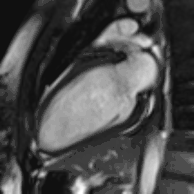

Heart function using cine imaging

Functional and structural information is acquired using bSSFP cine sequences. These are usually retrospectively-gated and have intrinsically high contrast in cardiac imaging due to the relatively high T2:T1 ratio of blood compared to myocardium. Images are typically planned sequentially to achieve the standard cardiac planes used for assessment. Turbulent flow causes dephasing and signal loss allowing valvular disease to be qualitatively appreciated. The left ventricular short axis cines are acquired from base to apex and are used for quantifying end-diastolic and end-systolic volumes, as well as myocardial mass. Tagging sequences excite a grid pattern that deforms with cardiac contraction allowing strain to be assessed.